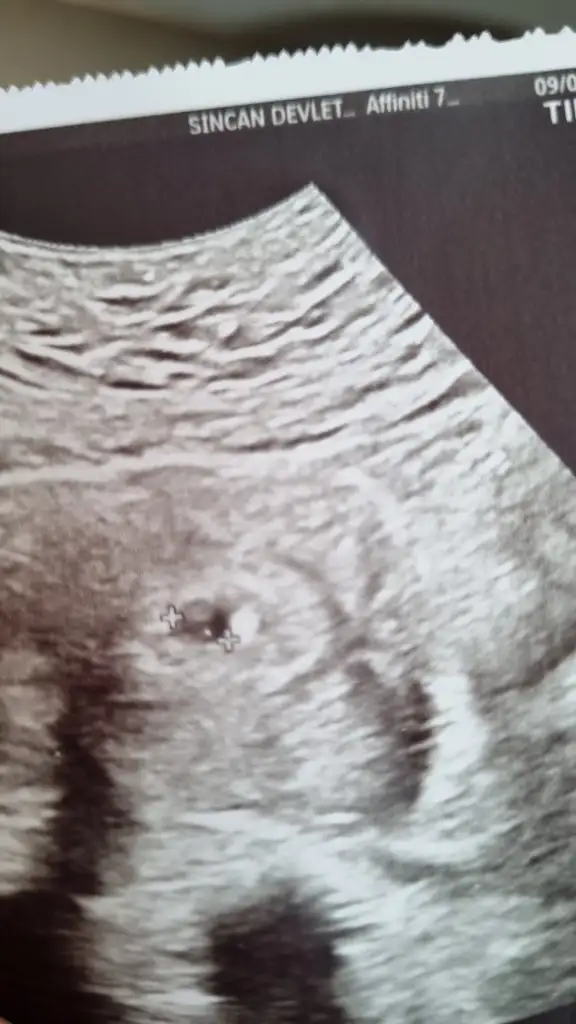

5+5 im suanda ve geceleri ates basması yasiyorum.. Sabah namazlarindan sonra mide bulantisi birakmiyor beni. Bir kabizim bir normal. Zfol iciyorum takviye olarak. Dun keseyi gormek icin doktora gittim. Biraz yakininda miyomun var rahminin icinde dedi. Buyuk nu dedim kucucuk dedi ama yuzu asildi moralim perperisan.. Resimdeki de benim bebisim daha cok kucuk :)